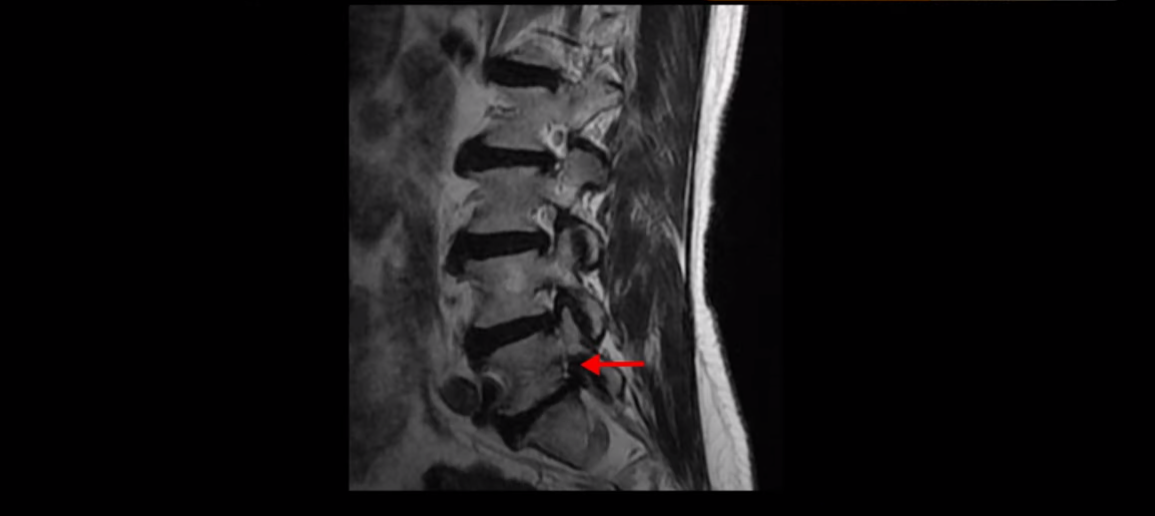

먼저 이분 MRI 보면서 간단히 설명 드린 후 어떻게 신경이 눌려서 수술해야 된다는 환자를 수술 없이 치료할 수 있는지 또 치료는 어떻게 하는지 자세히 설명 드리겠습니다. 이분 허리 MRI를 보면 여러 마디가 퇴행되어 있고

하지만 이 디스크 파열은 오래된 걸로 보이며, 지금 이 환자분의 아픈 양쪽 다리 특히 양쪽 발의 통증, 발 시린 증상과는 관련이 없어 보입니다. 오른쪽 왼쪽의 신경가지가 빠져나가는 추간공을 보면 오른쪽은 5번 1번과 4번 5번이 많이 좁아져 있고

왼쪽은 5번 1번이 많이 좁아져 있습니다.

이렇게 오른쪽 왼쪽 양쪽 추간공들이 다 좁아져 있고 신경가지들이 눌려있으니까 양쪽다리와 양쪽 발이 저리고 시리고 아파서 걷기 어렵습니다. 그런데 이 환자분은 신경주사를 여러 번 맞아도 듣지를 않는데요. 이렇게 신경주사가 듣지 않으면 십중팔구 수술밖에 방법이 없다는 얘기를 듣습니다. 그럼 어떻게 이런 신경이 눌려있는 환자분들을 수술 없이 치료해서 잘 걷게 만들고 다리와 발이 저리고 시리고 아픈 증상이 사라지게 만들까요? 지금부터 설명해드립니다.